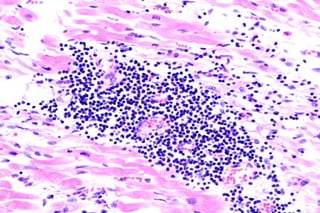

Biopsia miocardica: analisi istologica

e molecolare

Classici criteri istologici di Dallas

Presenza di cellule infiammatorie associata a necrosi

miocitaria nella stessa sezione microscopica di una

biopsia miocardica

La forma borderline e’ caratterizzata da un infiltrato di

cellule infiammatorie in assenza di necrosi

Questi criteri sono stati criticati perchetroppo restrittivi

>> si e’ giunti ad una definizione piu’ ampa che comprende

la presenza di genoma virale o marcatori molecolari di

attivazione immunitaria

Biopsia miocardica: analisiistologica e molecolare • Reperti istologici compatibili con i criteri di Dallas • Presenza di genoma virale rilevata mediante PCR o ibridazione in situ

• 53.

Classici criteri istologicidi Dallas Presenza di cellule infiammatorie associata a necrosi miocitaria nella stessa sezione microscopica di una biopsia miocardica La forma borderline e’ caratterizzata da un infiltrato di cellule infiammatorie in assenza di necrosi Questi criteri sono stati criticati perchetroppo restrittivi >> si e’ giunti ad una definizione piu’ ampa che comprende la presenza di genoma virale o marcatori molecolari di attivazione immunitaria